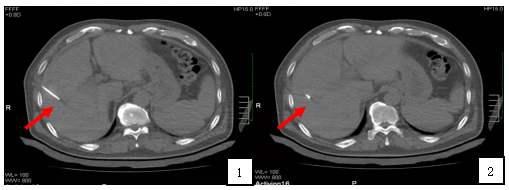

2. 2019-4-11 给予完全消融治疗:

采用射频消融(Cool-tip单针)治疗。患者平卧位,右手抱头,术前CT扫描,进行病灶定位,设计穿刺路线;局部皮肤麻醉,配合静脉镇痛,沿定位点,分步穿刺进针,再次CT扫描,确认消融针活性端穿刺至病灶处(见附图4箭头所示),开始消融治疗,条件:功率120W,时间8分钟。术毕,边消融针道,边撤针,局部无菌敷料固定。术毕再次CT扫描,以明确是否出现即刻并发症。术中及术后密切监测患者生命体征。

附图4:肝肿瘤消融术治疗布针情况。